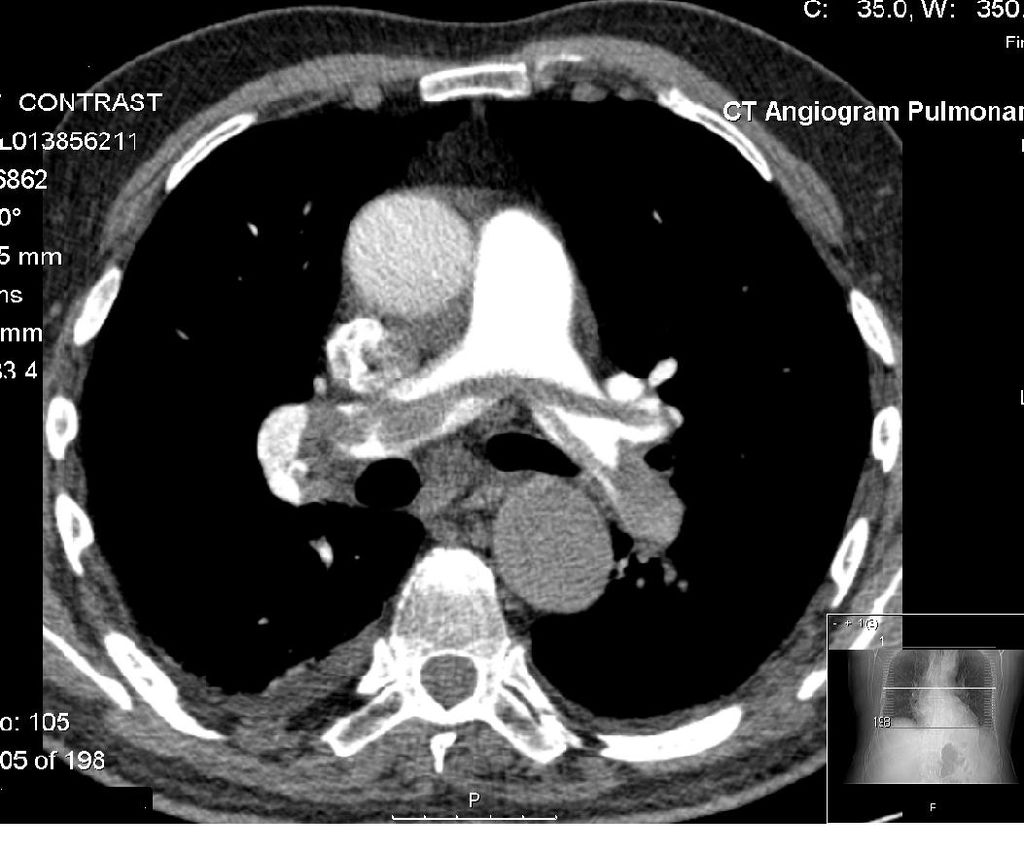

Diagnosed PE!

- Pneumonia

- Pulmonary Embolism